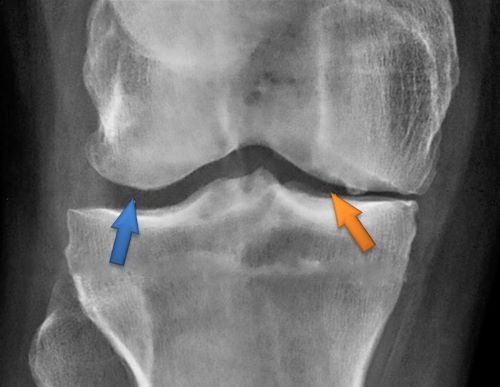

Пациент выполнил рентгенографию коленного сустава, на которой выявлен артроз коленного сустава 3-й стадии.Лечение